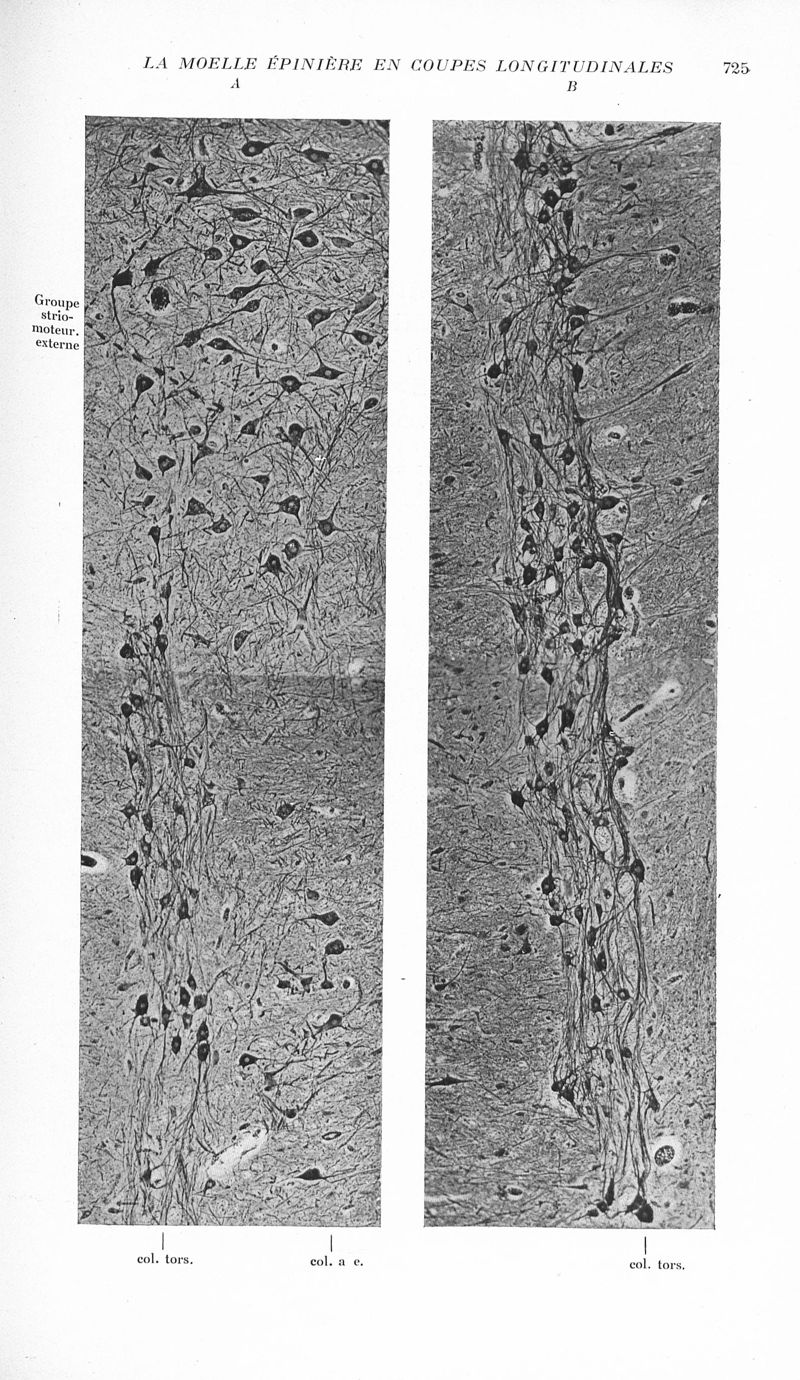

Revue neurologique

1937, vol 1. - Paris : Masson , 1937.